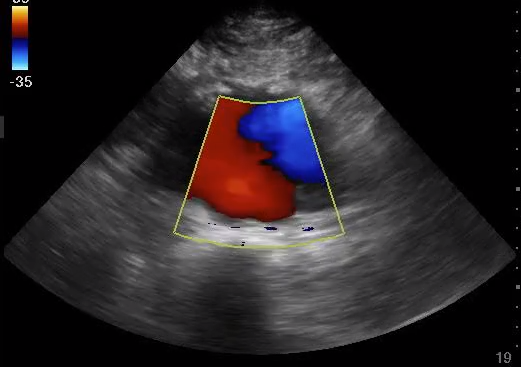

Read MoreJoin us for a comprehensive review of the state of the art (and literature) of POCUS in cardiac arrest